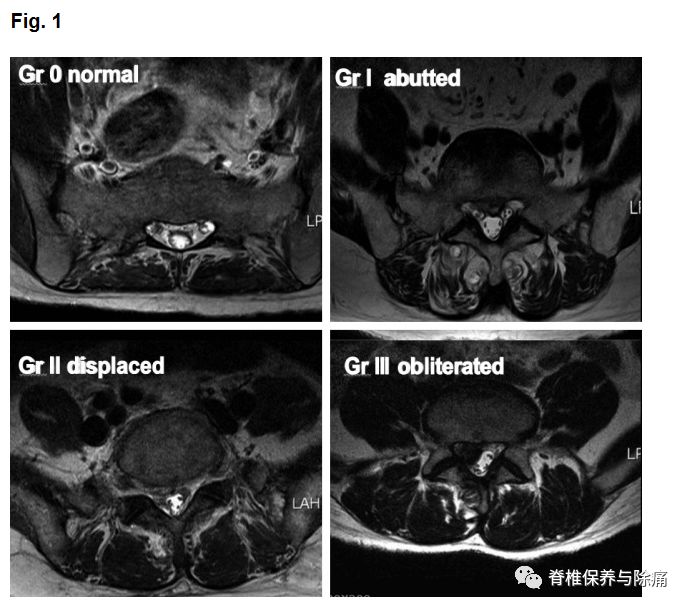

术前症状侧的神经根的轴位MRI和CTM扫描,根据严重程度病理程度分为四级0级:没有神经根受压(根映像是可视化); I级:神经根被激惹;II级:神经根移位或变形;III级:确定的神经根被压缩。

The root imageson the preoperative axial MRI and CTM scans of the symptomatic side at thepathological level were classified into four grades according to the severityof nerve root compression by modifying a previous grading system as follows:grade 0, no nerve root compression (root image is well visualized); grade I, nerveroot is abutted or contacted; grade II, nerve root is displaced or deformed;and grade III, definite root compression or completely nonvisualized (flattenedor obliterated) root image1

A:不激惹神经根(0)级。B:神经根毗邻但不显示任何激惹或变形的迹象(I级)。C:神经根移位,压缩变形(II级)。D:明确的神经根受压的神经根(III级)。E: 侧隐窝无激惹神经根(0)级。F:三侧隐窝三叶草形态变化 (I级)。G: 侧隐窝变尖(II级)。H: 侧隐窝三叶草形缩小, 神经根移位及变形(II级)。I: 侧隐窝夹角变尖, 神经根移位机变形 (II级)。J:严重的侧隐窝夹角变尖,扁平的神经根(III级)。K: 侧隐窝不见神经根(III级)。

Gradingof nerve root images in the herniated nucleus pulposus and lateral recessstenosis. A: No compromise of the nerve root (grade 0). B: The nerve root isabutted but does not show any signs of deviation or deformation (grade I). C:The nerve root is displaced (deviated) and deformed by compression (grade II).D: Definite nerve root compression with the nerve root completely nonvisualized(grade III). E: No compromise of the nerve root in the lateral recess (grade0). F: Trefoil-shape change of the lateral recess (grade I). G: Early acuteangular narrowing of the lateral recess (grade I). H: Trefoil-shape narrowingof the lateral recess, and displaced (deviated) and deformed nerve root (gradeII). I: Angular pinch-like narrowing of the lateral recess, and displaced(deviated) and deformed nerve root (grade II). J: Severe angular pinch-likenarrowing of the lateral recess and flattened nerve root (grade III). K: Theroot image is completely nonvisualized in the lateral recess (grade III).